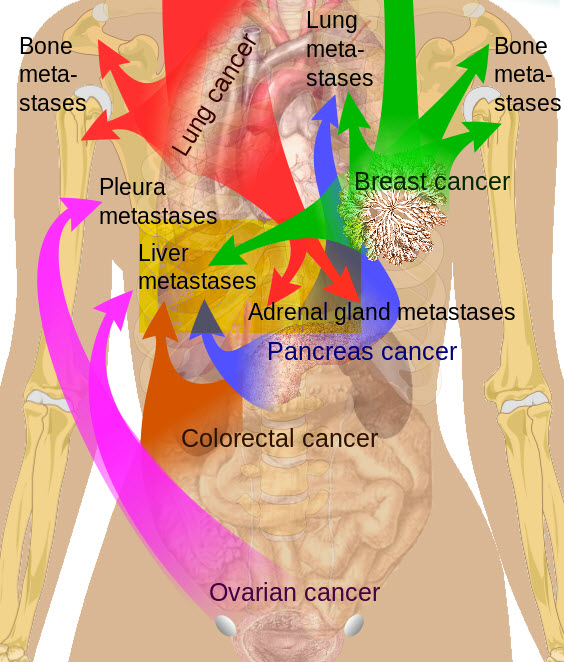

Click here or image for full body view

| Main sites of metastases for some common cancer types, showing liver as the target for many types. Primary cancers are denoted by "...cancer" and their main metastasis sites are denoted by "...metastases. Image courtesy of Mikael Häggström / Wikimedia Commons / CC-BY-SA-3.0 |

After the lymph nodes, the liver is the most common site of metastatic spread. Most liver metastases originate from the colon, rectum, pancreas, stomach, esophagus, breast, lung, melanoma and some less common sites.

Several factors influence the incidence and pattern of liver metastases. These include the patient's age and sex, the primary site, the histologic type, and the duration of the tumor. In a few tumor types, such as colonic carcinoma, carcinoid, and hepatocellular carcinoma (HCC), metastasis is confined to the liver. Most tumors that metastasize to the liver, such as breast and lung cancers, spread to other sites at the same time.